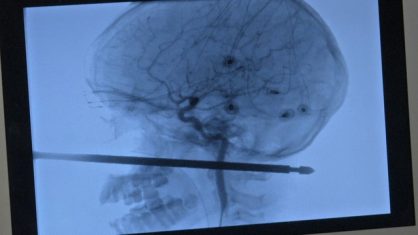

A ponta fina do espeto atravessou sua cabeça e “milagrosamente” não atingiu seus olhos, cérebro, medula espinhal e principais vasos sanguíneos.

Segundo relato de familiares ao hospital, o garoto estava brincando numa escada e, ao escorregar, caiu em cima de um tonel que era usado para guardar espetos